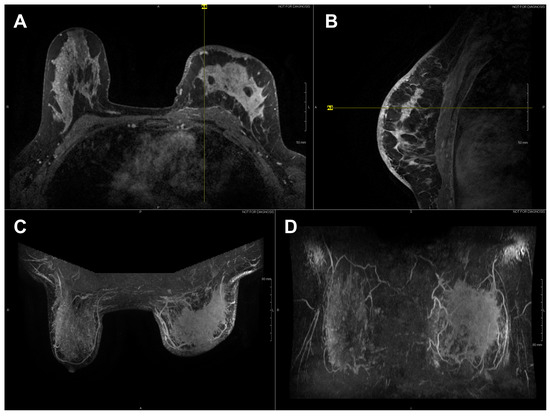

| 04 * | Malignant | Left | Phyllodes | High | 17.5 cm (mammo) | Mass occupied entire breast | – | – | Non-mammary origin (stromal cancer) |

| 09 | Malignant | Left | IDC | 3 | 3.6 cm (US) | 12:00, 2 cm, from nipple (dominant mass) UOQ, 1:00, 2 cm from nipple (satellite mass) | ER+, PR+, HER2/neu+ | 2b | – |

| 10 | Malignant | Right | IDC | 3 | 4.4 cm (US); 5.2 cm (MR) | UIQ, 1:00, 2 cm from nipple (dominant mass) UIQ, 2:00, 8 cm from nipple (satellite mass) | ER−, PR−, HER2/neu− | 3b (inflammatory) | Triple negative |

| 11 | Malignant | Left | IDC (NOS) | 3 | 8 cm (mammo) | UOQ, 2:00, 4 cm from nipple (dominant mass) UOQ, 2:00; UIQ, 10:00 (satellite masses) | ER−, PR−, HER2/neu− | 2b | Triple negative; multiple adjacent satellite masses |